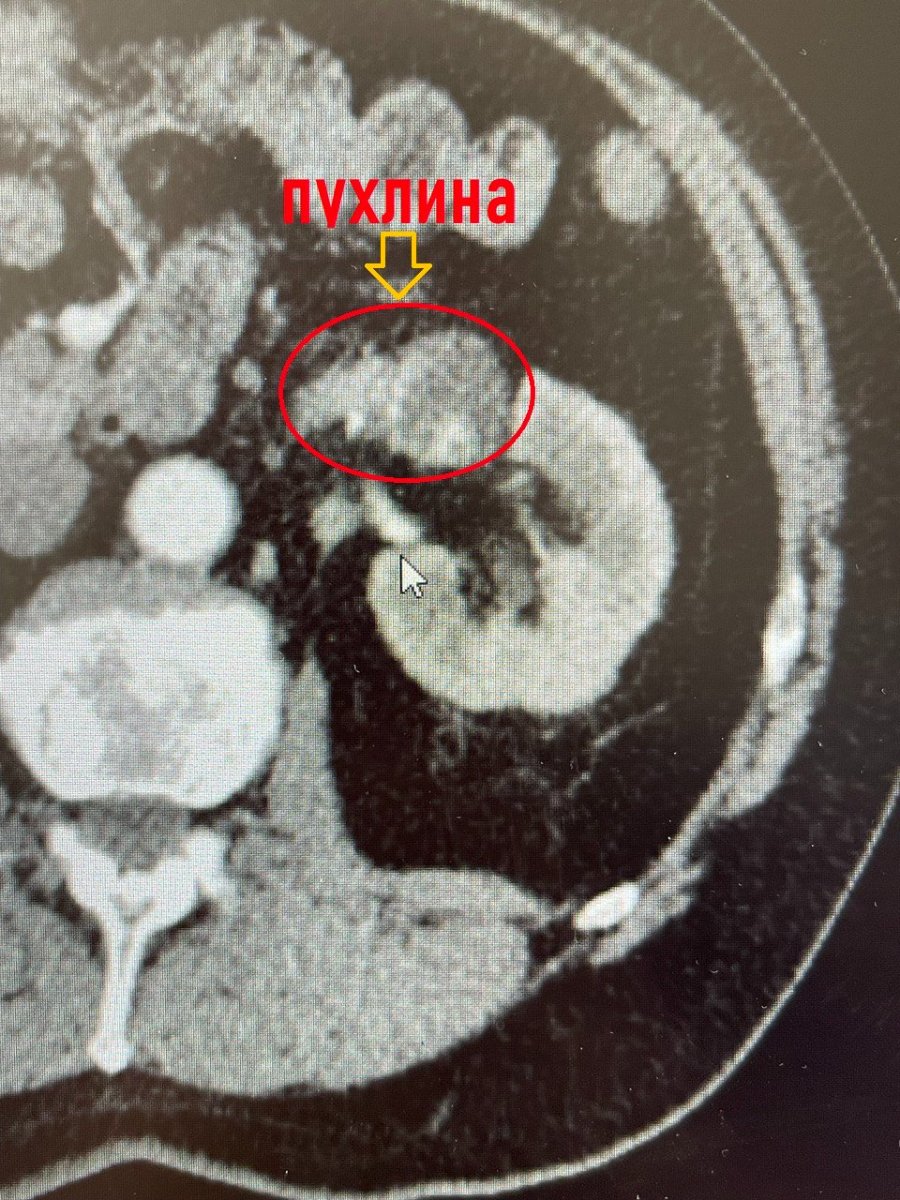

Обстеження на комп’ютерному томографі показали наявність в нирці коралоподібного каменя розміром 38х28 мм та доброякісного пухлинного утвору до 3 см в діаметрі з неоднорідним кровотоком у центрі, який знаходився на судинній ніжці лівої нирки.